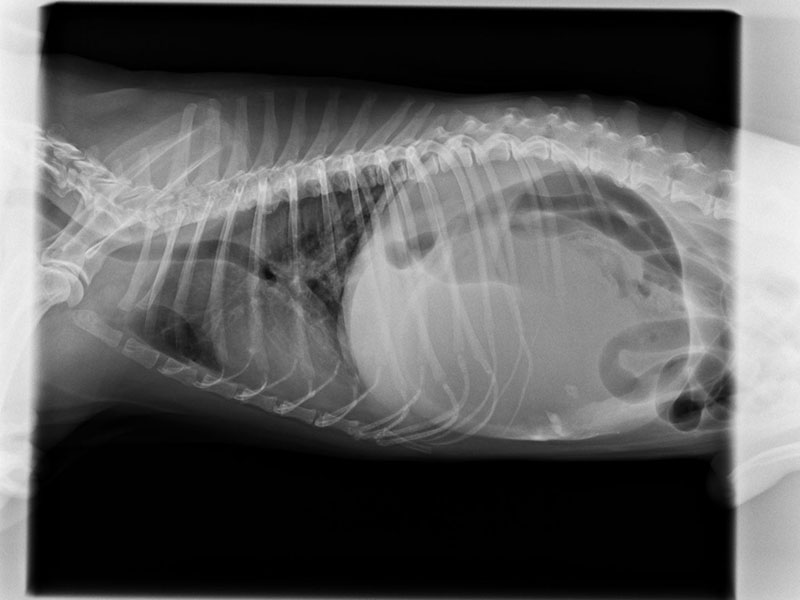

胃扭轉(GDV).

凌晨兩點就診的點點因為罹患胃扭轉(GDV)而不適,幸好半夜有即時就診手術校正,住院3天後就平安出院;如果拖到隔天早上才手術可能就沒有那麼幸運了喔!